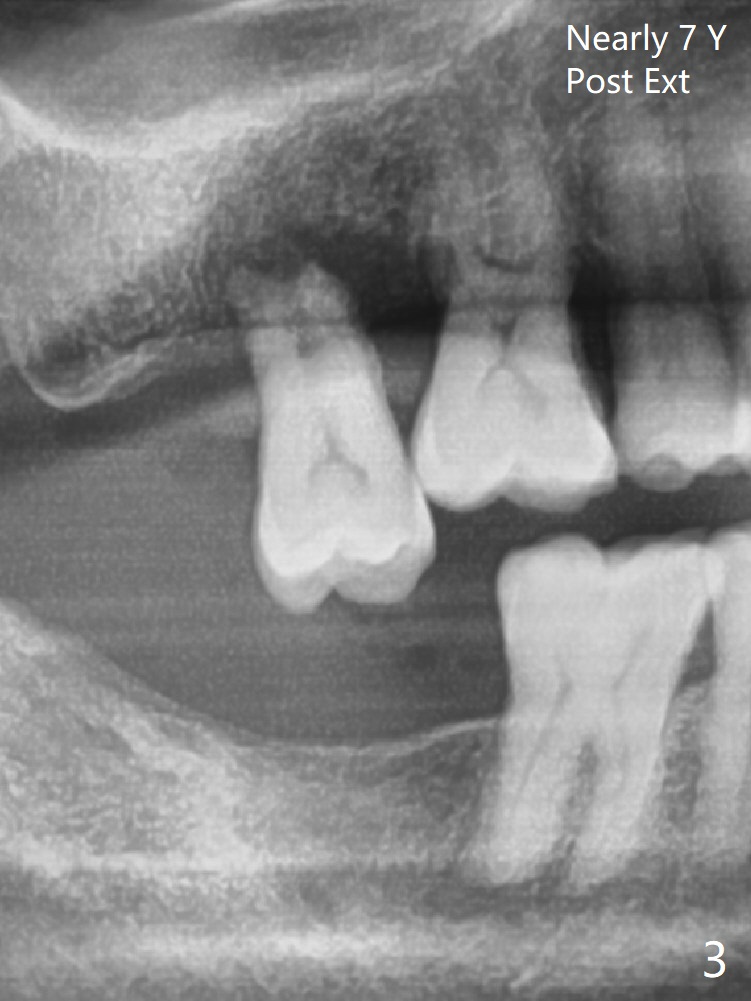

A 62-year-old man does not masticate on the right side due to facial paralysis (Fig.1 (pan taken ~ 8.5 years earlier)). Two years 9 months post #31 extraction, the tooth #2 has supraerupted (Fig.2). Nearly 7 years post extraction of #31 (Fig.3), the patient requests extraction of the supraerupted tooth because of repeated infection (Fig.4 distal view of the extracted tooth). There is calculus in the furca between the palatal (P) and buccal (B) roots. To facilitate bone regeneration in the distal surface of the tooth #3, Osteogen plug is placed in the distal portion of the socket of #2 (Fig.5 O), while allograft in the mesial one (*).